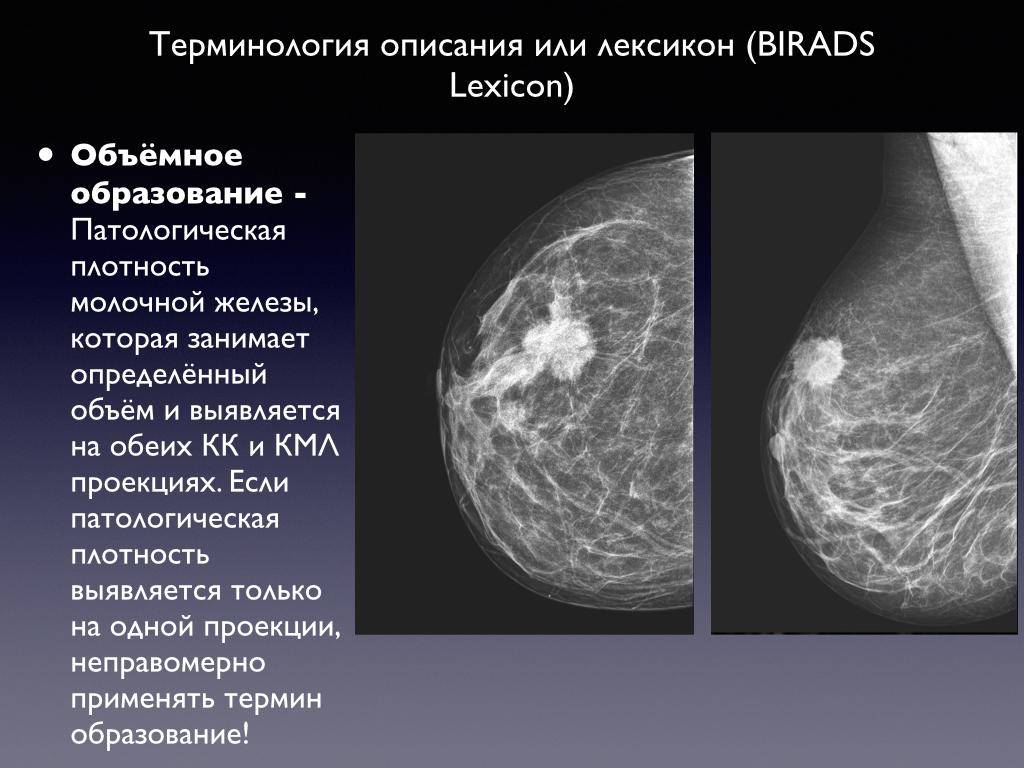

Феномен гипердиагностики в маммографии: примеры и иллюстрации

Раздел: Образы вокруг